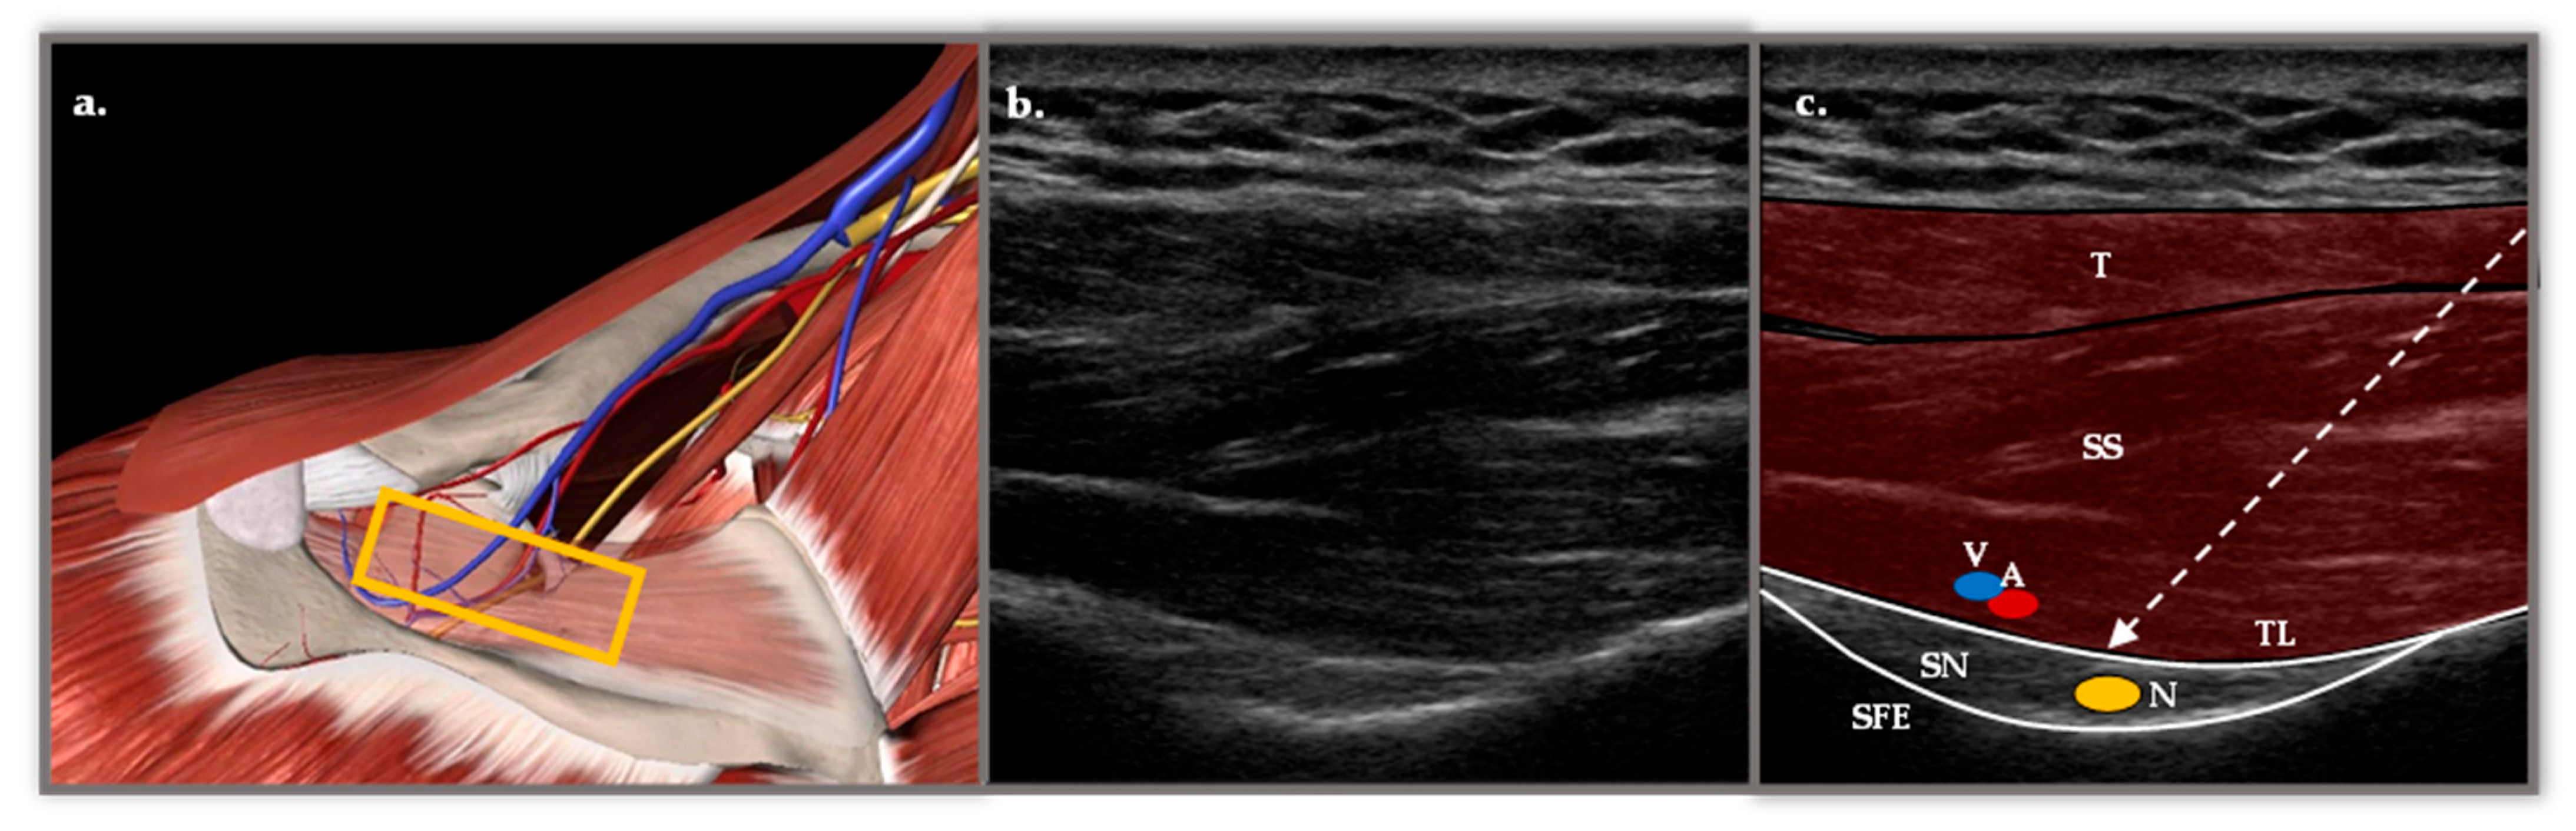

The basic foundation of this technique lies in the sensory innervation of the shoulder, which accounts for almost 70% of the suprascapular nerve [15], specifically the posterior-superior area of the rotator cuff [17]. SSNB can be performed using different approaches, either based on anatomical landmarks or guided by ultrasound (US), a method that offers greater precision and safety [18]. The approach used in the Physical Medicine and Rehabilitation (PM&R) Department of the Reina Sofía University Hospital (HURS) is the posterior medial-to-lateral approach with US. Figure 1.

Figure 1.

(a) Anatomical representation in Essential Anatomy 5 of the approach to the SSBN in the supraspinatus fossa. The muscular plane of the trapezius (T) has been removed and the supraspinatus (SS) has been faded, revealing the depth of the suprascapular nerve (N), vein (V) and artery (A) in the scapular notch (SN). The yellow rectangle represents the longitudinal position of the probe. (b) Longitudinal ultrasound section with a 6 and 15 MHz flat probe in supraspinatus fossa. (c) Representation of the most important structures with two muscle layers corresponding to the T and the SS. Below, two hyperechoic structures appear, the transverse ligament (TL) and the SE, which form the roof and floor of the fossa through which the N passes. The TL separates the V and A structures from the N. The dashed arrow represents the course of the needle with a posterior approach from medial to lateral.